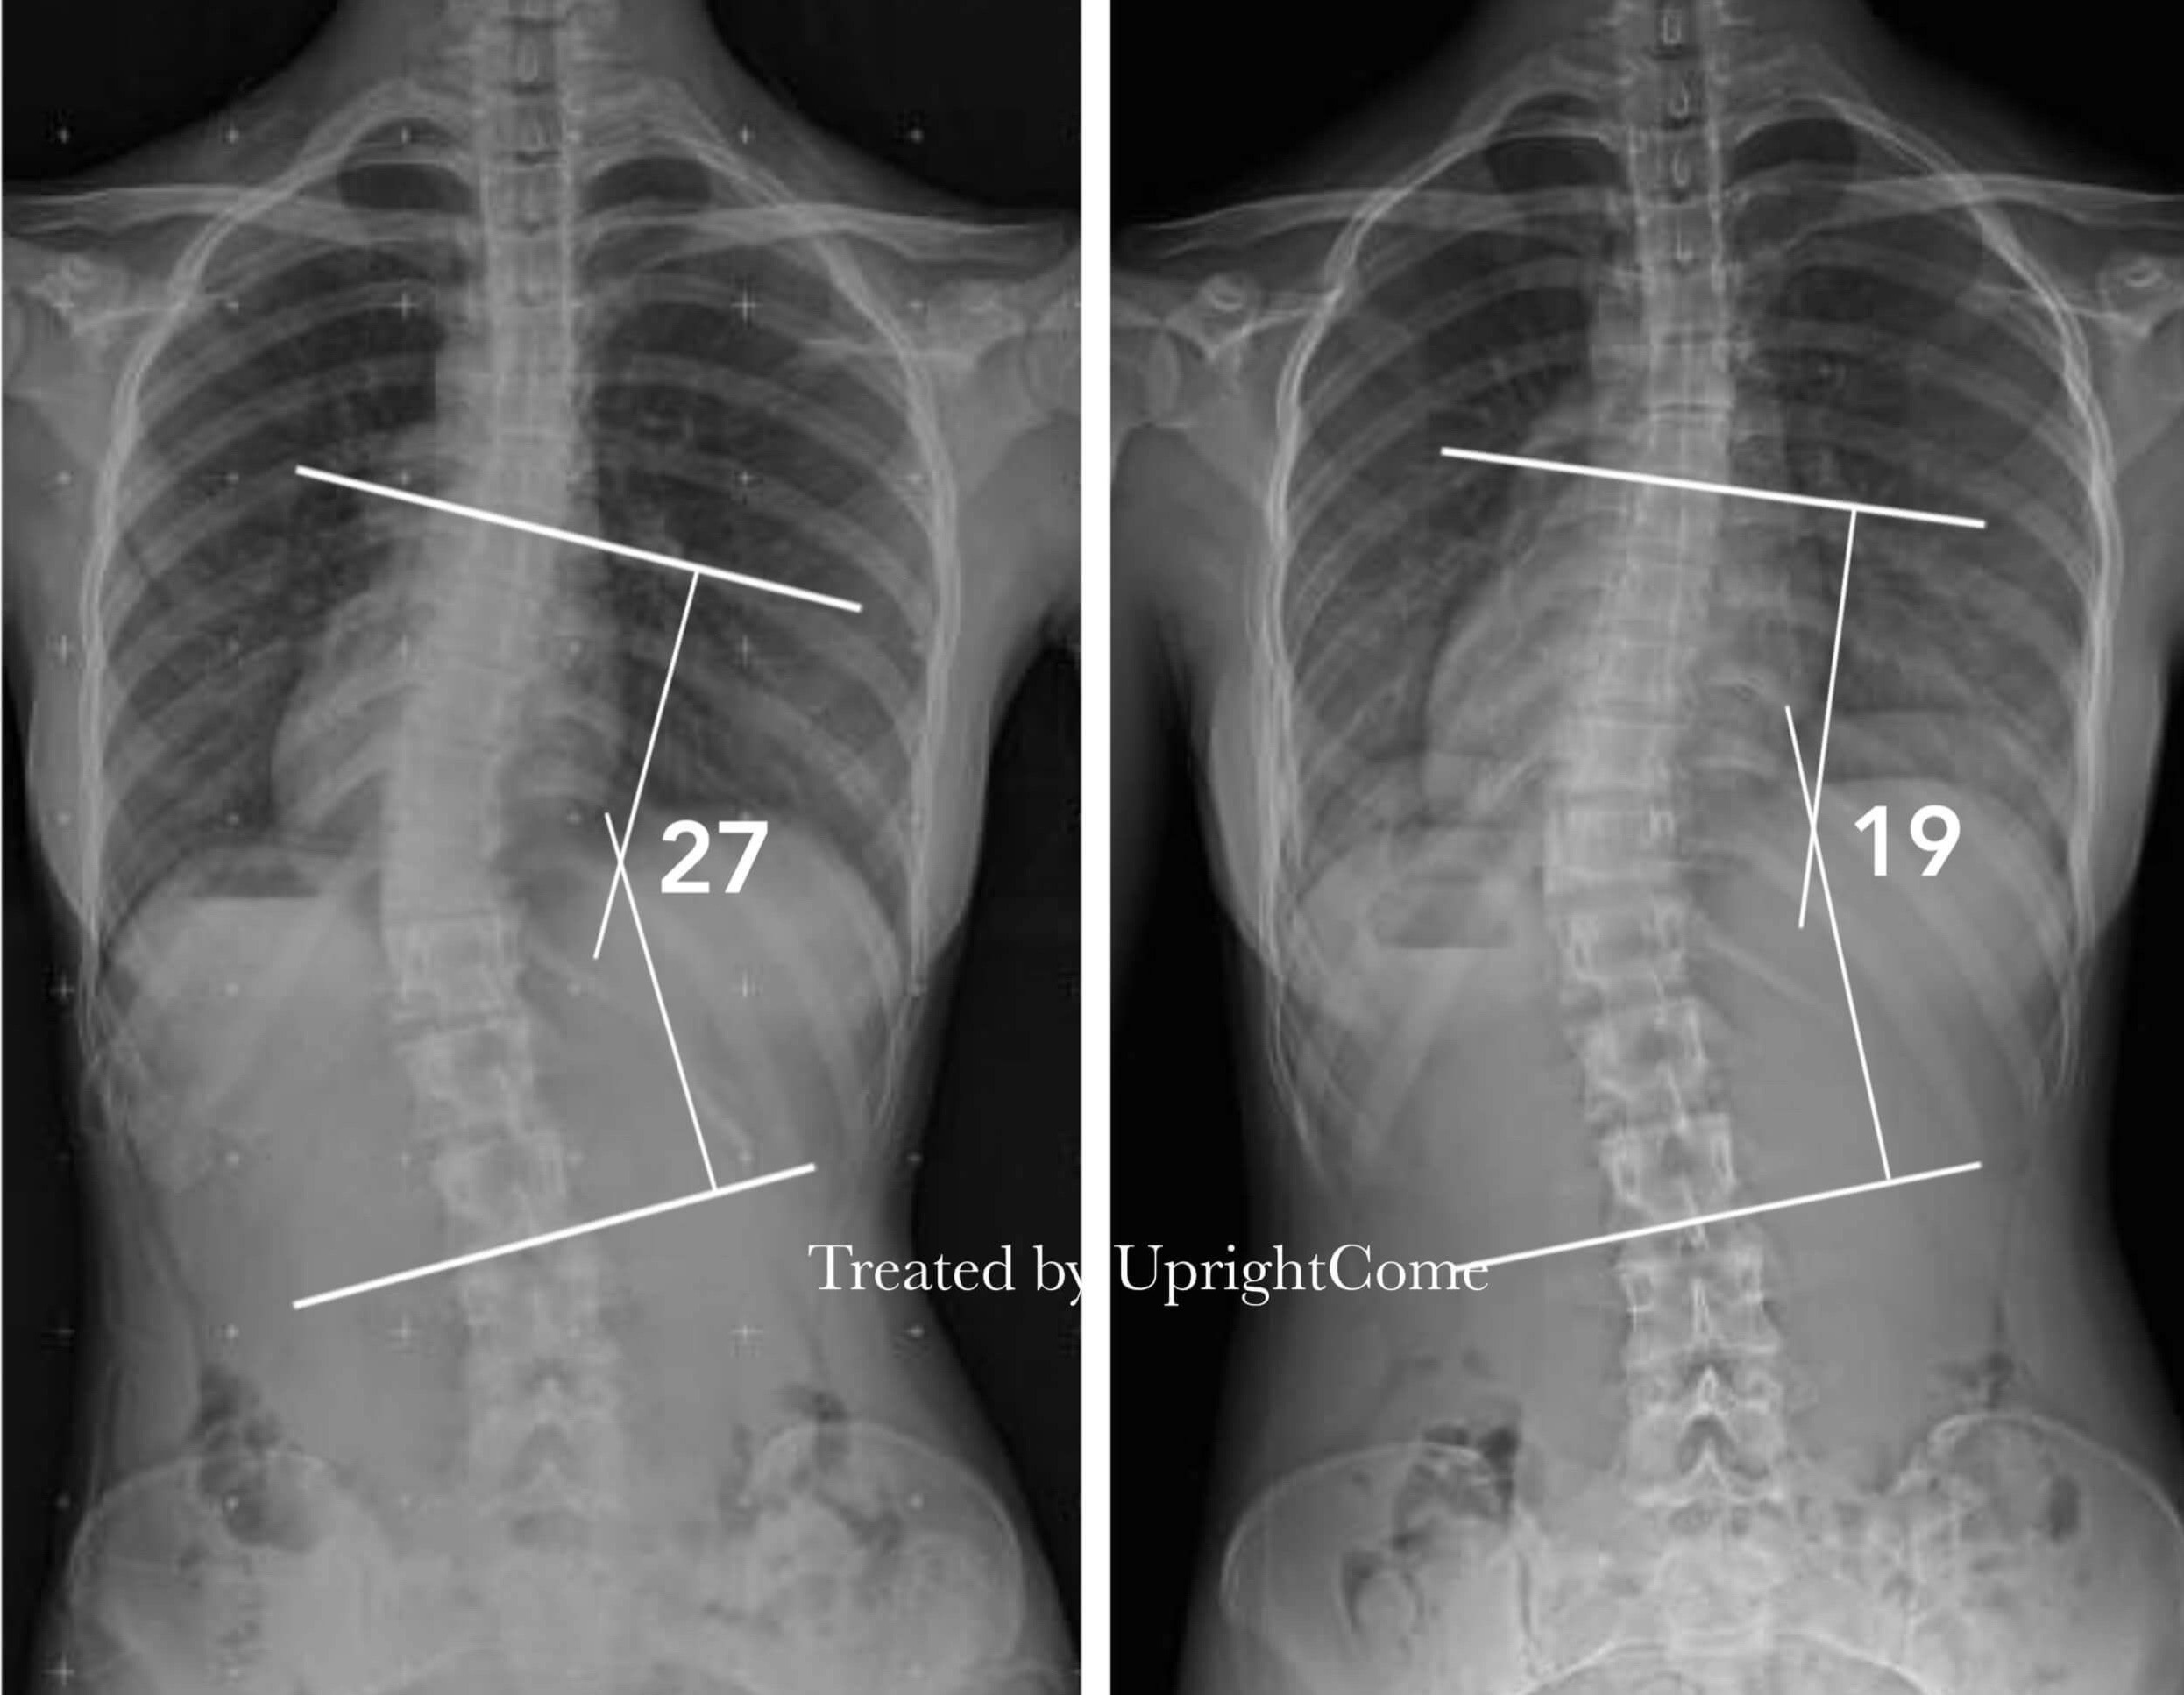

Case 14, 16 years old, 38° Cobb

![脊椎側彎患者經過側彎矯正治療後,胸椎側彎角度由38度減少到21度。]()